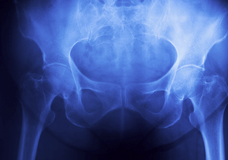

고관절은 대퇴골과 골반의 뼈가 만나는 관절로, 인체에서 가장 큰 관절 중 하나입니다. 대퇴골의 머리 부분은 골반에서 발생한 홈에 맞게 끼워지며, 관절 내부에서 연결되어 있습니다. 고관절은 운동 기능에 매우 중요한 역할을 하며, 다리의 움직임과 몸의 균형을 조절합니다. 고관절은 일상생활에서 매우 많이 사용되기 때문에, 나이가 들거나 과도한 운동, 부상 등으로 인해 손상될 수 있습니다. 고관절의 질환이나 손상은 통증, 제한된 움직임, 앉기와 일어섬에 어려움 등을 유발할 수 있으며, 가장 심각한 경우에는 관절 교체 수술이 필요할 수 있습니다. 고관절의 건강을 유지하기 위해서는 적절한 운동, 체중 관리, 건강한 식습관 등이 중요합니다.

고관절 정보